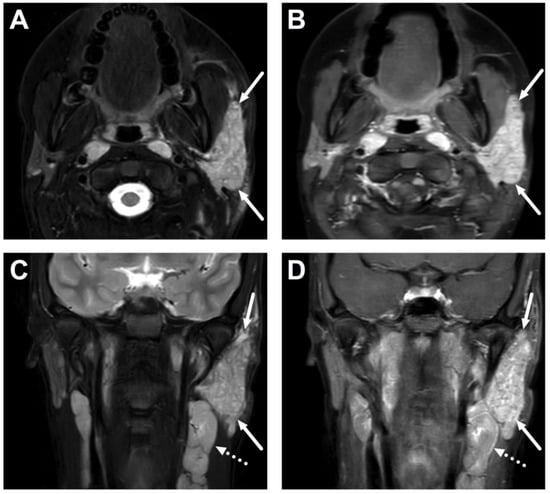

4.1. Tonsillitis, Peritonsillar Abscesses, and Parapharyngeal Abscesses

4.2. Retropharyngeal Abscesses and Suppurative Lymphadenitis